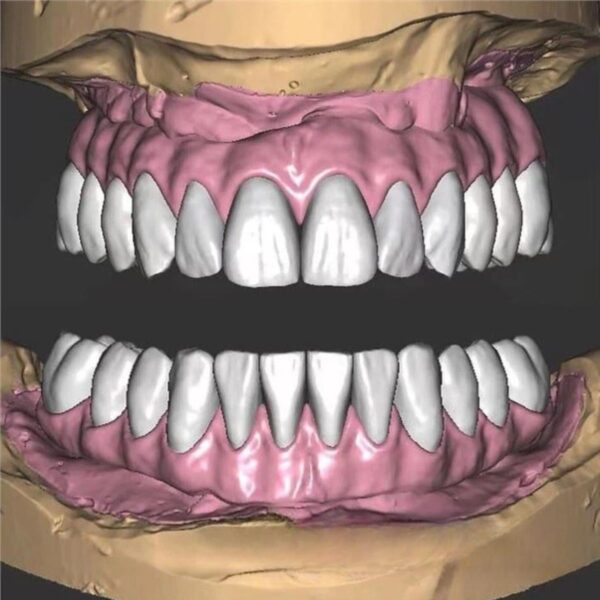

China Dental Design Complex Case Gallery

Challenging Projects That Showcase Our China Dental Design Expertise

Dental Model and Denture Design

Advanced China Dental Design Capabilities

Our expert China Dental Design team delivers precision, quality, and cost-effectiveness for every complex restoration project

Specializing in:

- Full mouth rehabilitations

- Multi-unit implant bridges

- Aesthetic zone reconstructions

- Complex occlusal cases